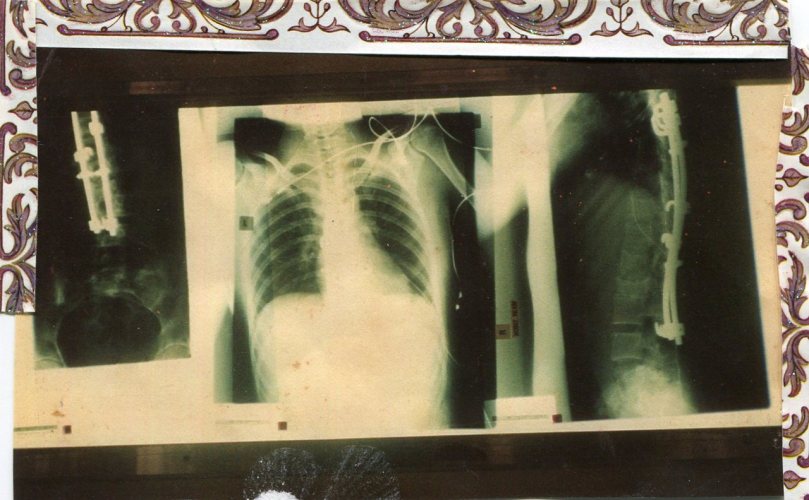

Being told I was stupid. I lost so much time at school in primary and high school, due to being drugged or being  in hospital. I was told I was stupid and wouldn’t amount to anything in Year Seven. When you are told often enough, you tend to start believing it. They were wrong. A kid who isn’t clever couldn’t have survived the years that followed. I left school at fourteen, when I was put in the clinic, and was extremely nervous when I was signed up to Distance Education by my surgeon when I was fifteen years of age. I was in my rotor bed when the first pack of lessons arrived. To my astonishment, not only did I enjoy it, but I was also good at it. The teachers were encouraging, and I knew I had been lied to about my intelligence and ability to learn. I am so grateful that I had the opportunity to find out. Don’t believe them when they label you, please don’t absorb it!

Surviving it all! I am still amazed by the dawn of each new day. Amazed that I am here to see it. To have survived is extraordinary. I have my medical notes, and at times, the prognosis was grim. Here I am, an intelligent woman in her thirties, who smiles more than she frowns. Who plans for the future, and has left the pain behind. There was no magic secret I uncovered. It had to do with giving myself a break, understanding myself on a deep level, and kindness. With self-love and kindness, the healing begins. You define who you are, not them. xxx